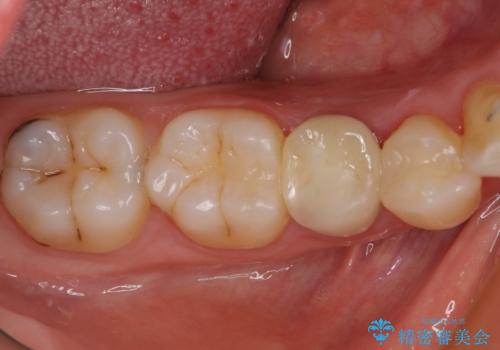

- 神経を抜く処置の後に装着したプラスチックのクラウンが外れてしまったとのことで来院された患者様です。

患者様自身、神経の取り除かれた歯はしっかりと製作されたクラウンを装着するべきと理解していただいていたため、オールセラミッククラウンにて補綴治療することとしました。

丈夫なクラウンを装着できただけでなく、形態や色調も自然に仕上げることができました。